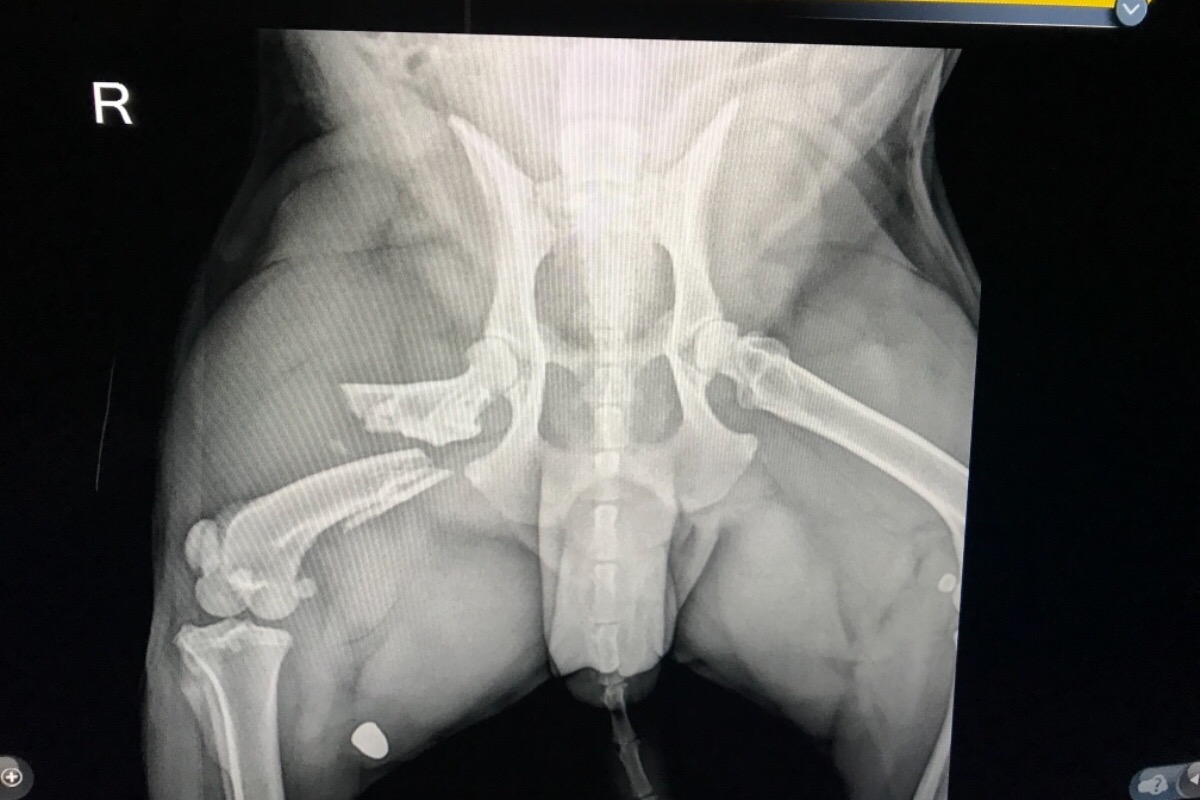

Photo Caption: Shattered Femur

On Tuesday, September 4, 2018, the earliest that a surgeon was available due to the Labor Day weekend, Sammy, our brave, heroic pit bull, underwent surgery. Sammy had to get the largest plate available to put his right leg back together. A rod and pin was installed to hold it in place. He also had to have shattered bone pieces removed from the injured area. The cost of the surgery is $12,000! He is back home and doing better. His recovery time will be a long 6-8 weeks. But that length of time is extremely short compared to the forever memory of what happened on Sunday. My family and I are still in shock and all kinds of emotions are flowing through us . . . especially fear, rage, and sadness.